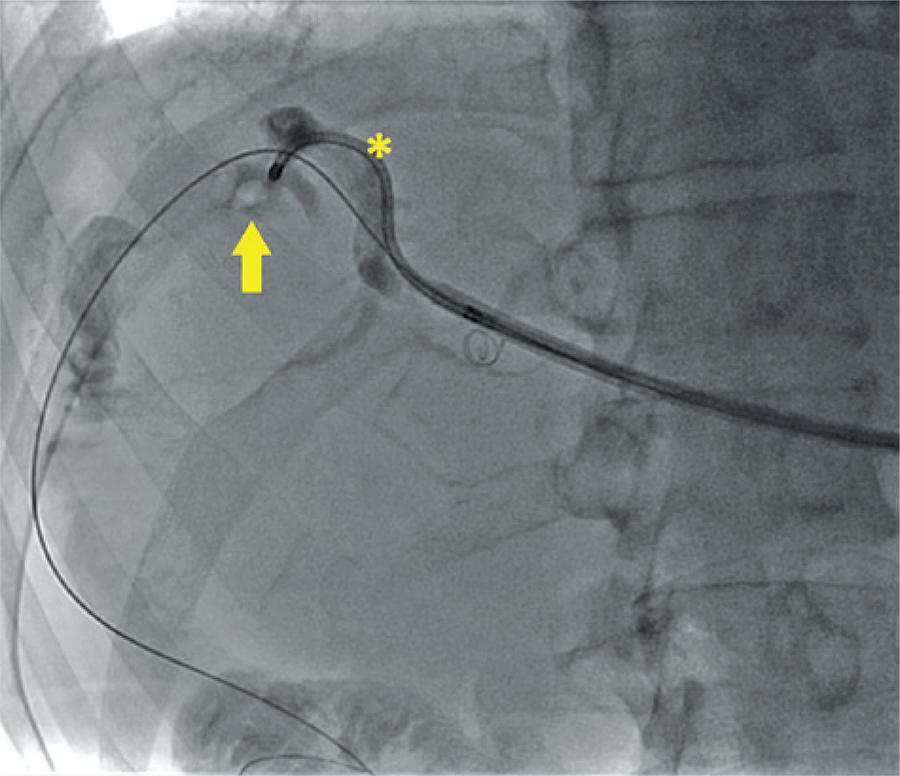

Tratamento percutâneo da litíase biliar complexa intra-hepática com técnica endourológica e revisão da literatura

A maioria das doenças litiásicas das vias biliares necessita de tratamento cirúrgico. No entanto, em casos especiais, que não permitem o acesso tradicional das vias biliares por via endoscópica, a abordagem multidisciplinar com técnica híbrida, que utiliza instrumentais endourológicos, apresenta-se como uma opção no tratamento. Relatamos aqui o caso de um paciente com litíase de via biliar complexa com múltiplas abordagens prévias, sem sucesso no tratamento com métodos convencionais, resolvido com abordagem híbrida com tecnologia endourológica. Realizamos uma extensa busca na literatura de artigos relacionados ao tratamento de litíase biliar complexa com técnica híbrida publicados no PubMed até outubro de 2012. A abordagem multidisciplinar com técnica híbrida, utilizando instrumental endourológico, representa uma opção segura e eficaz no tratamento de pacientes com litíase complexa de via biliar com impossibilidade de tratamento com métodos convencionais.